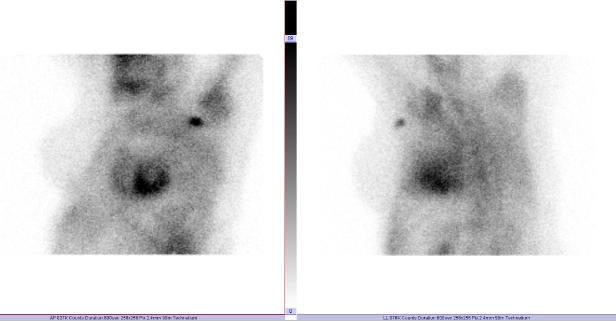

/ Obr. č. 1: Statická scintigrafie hrudníku v přední a levé boční projekci. Vyšetření 3 hodiny po aplikaci radiofarmaka.

Prokazujeme zvýšenou depozici radiofarmaka v myokardu levé srdeční komory. Zvýšená depozice je vyšší než v žebrech - dle semikvantitavní škály jde o stupeň 3.

Scintigrafickým vyšetřením potvrzujeme transthyretinovou srdeční amyloidózu.